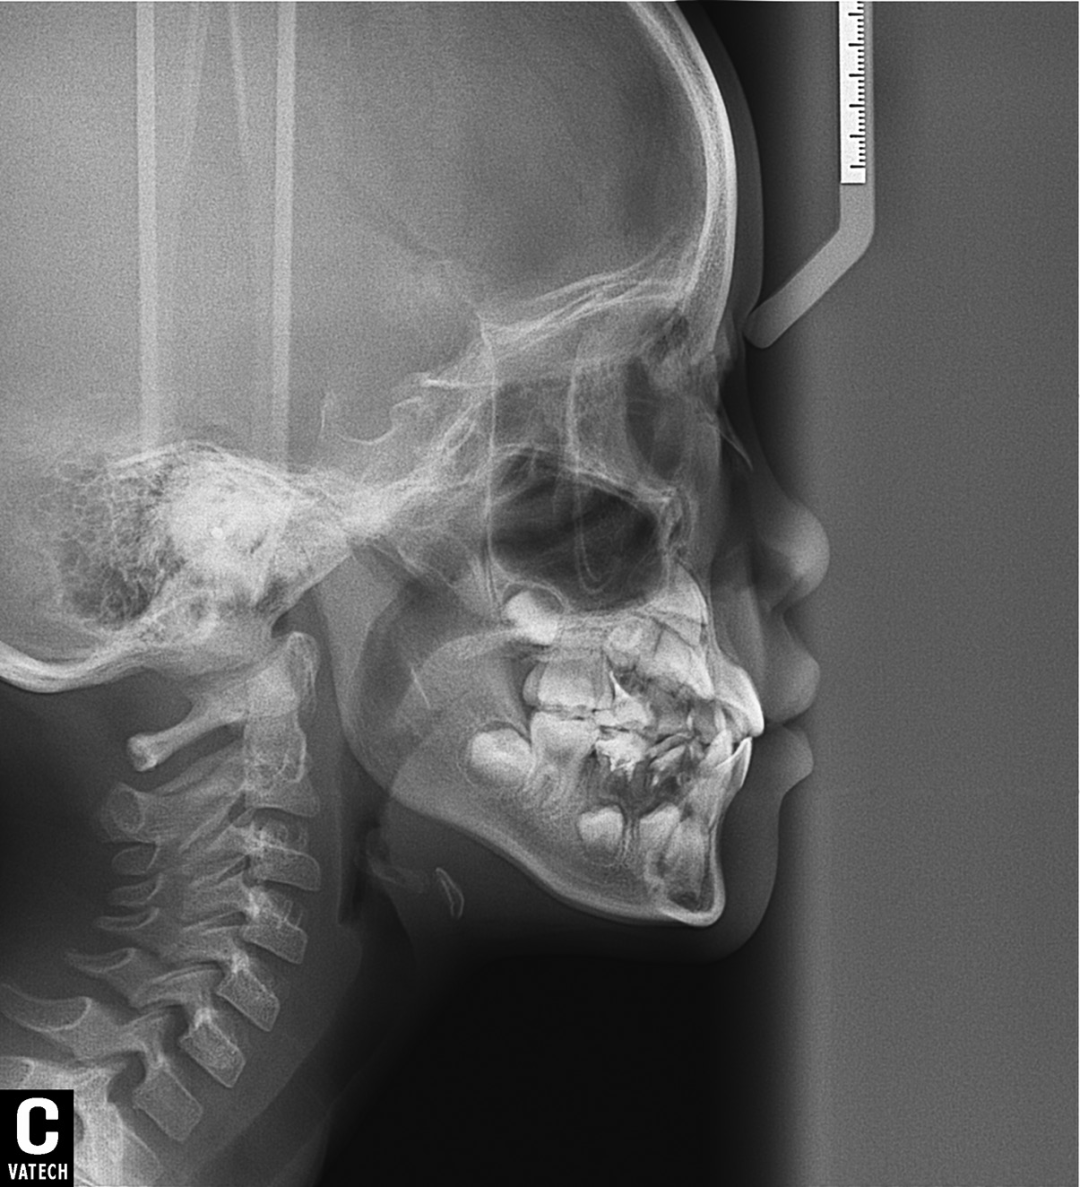

一般在替牙中期孩子上下4颗门牙换完,是比较好的干预时机,再就是女孩替牙晚期,只剩上下第二乳磨牙还没有脱落;男孩刚刚结束替牙期,正处于年轻恒牙列阶段,还有机会引导下颌向前生长。